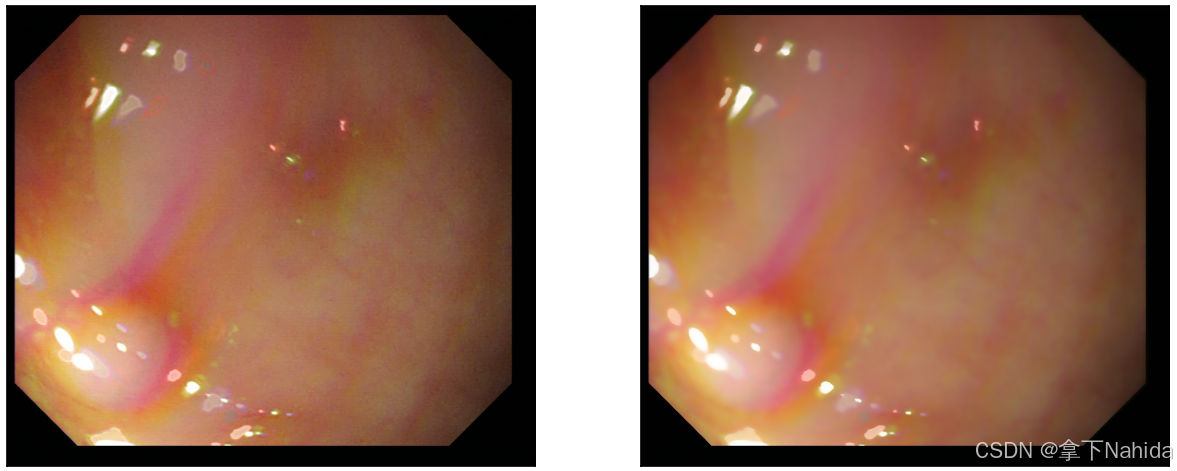

a.均值滤波

均值滤波是最简单的线性平滑滤波方法,它通过计算窗口内所有像素的平均值来代替中心像素的值,以此达到去除噪声的效果。

实例图如下。

看起来显得变得更模糊了,图像的颜色区间变化不那么尖锐,这样把噪点作出处理的同时牺牲了一定清晰度。